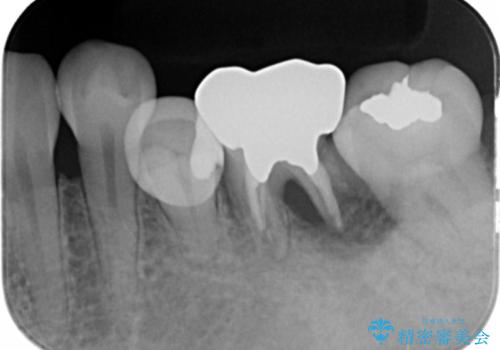

- 他院で矯正を終えた後、犬歯が尖っていることが気になるとのことで来院。

ラミネートベニア修復を希望されました。

2番の欠損により3113の並びになっており、かつ、裏側はワイヤーで固定してありました。

特に右の犬歯と前歯の間には隙間が残っていました。(裏側のワイヤー固定の接着剤で一見隙間がなさそうにカモフラージュしてあります?が・・・)

その部分は汚れが非常にたまりやすくなっていました。

オールセラミッククラウンも選択肢としてあげられましたが、歯の表側のみを削るラミネートベニア修復を選択されました。